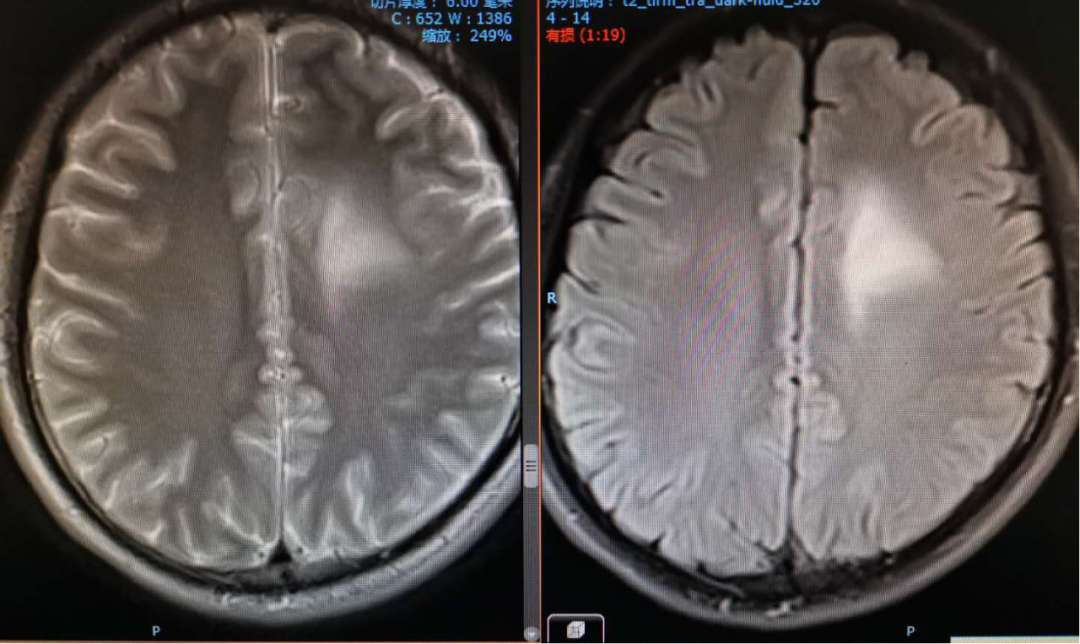

2020-01-06放疗后MRI

2020-4-23 MRI复查

复查MRI提示:局部病灶强化,PWI提示局部灌注有缺失,考虑病情进展,同时不除外假性进展,患者脑水肿范围较大。

根据以往经验调整治疗方案:1、根据复发胶质瘤相关指南,首选抗血管生成药治疗;2、MDT讨论:病灶累积胼胝体,再次手术难度大;3、给予“阿帕替尼425mg qd po”。之后显示水肿变小,灌注降低。继续原方案治疗。